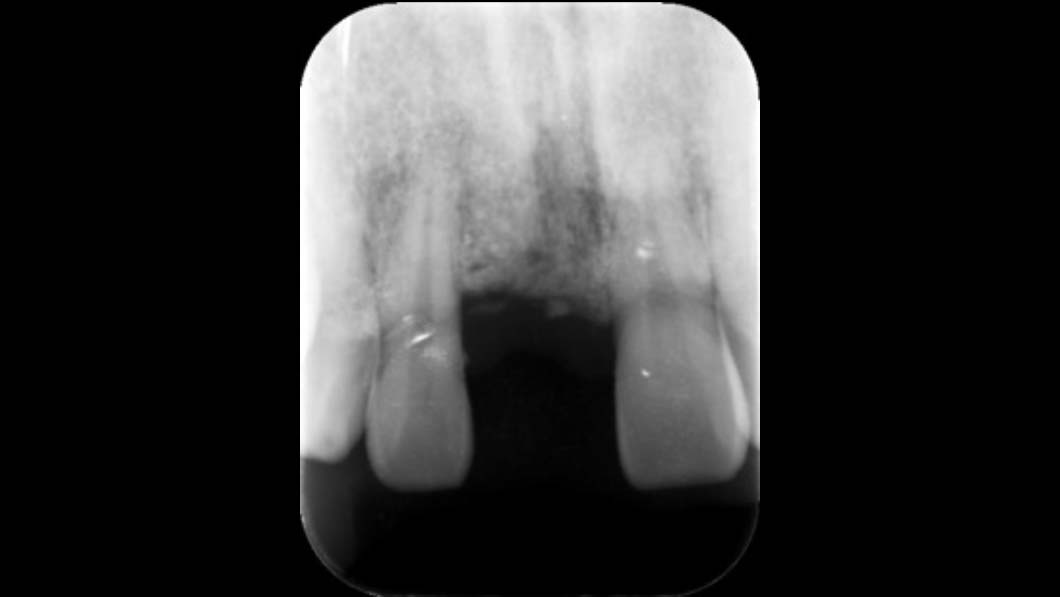

- 右上1を抜歯しソケットプリザーベーション(抜歯したまま放置すると骨が高度に吸収してしまうため、それを予防するための処置)を行い、隣在歯と骨レベルを合わせたのちにインプラント埋入を行った。

インプラントは理想的な状態に仕上がり、他の歯のクラウンも美しく調和することができた。患者さんも非常に満足度がたかかった。